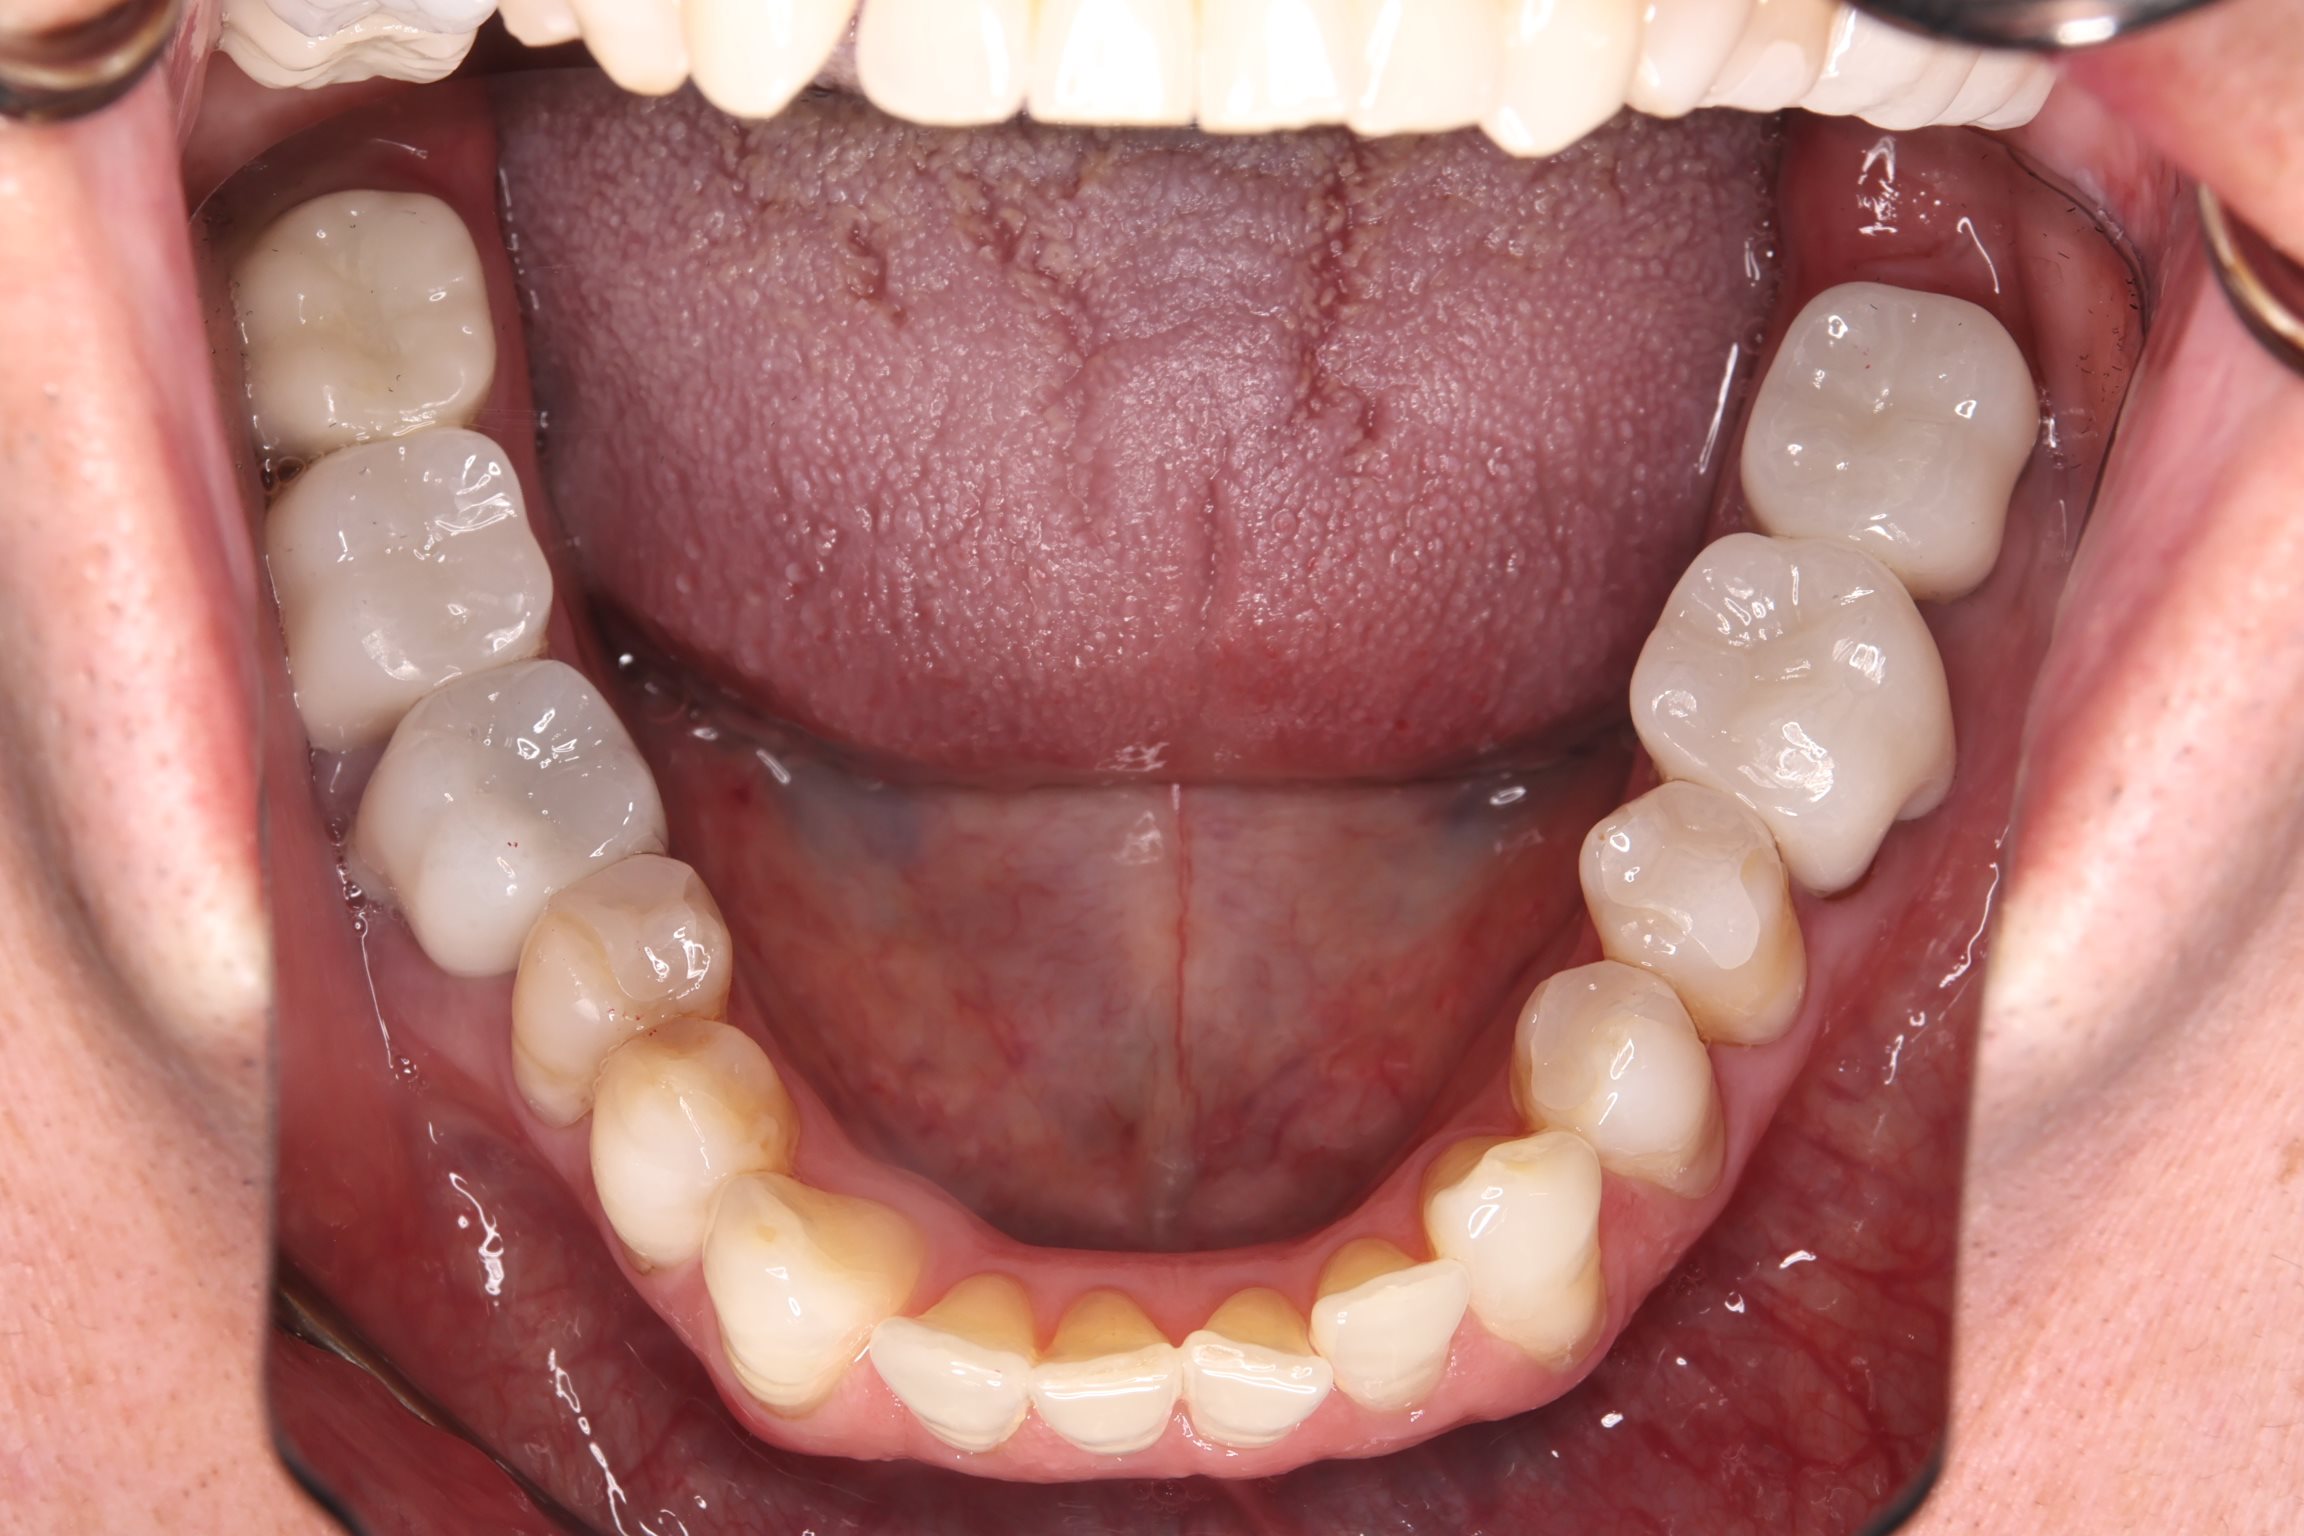

治療結果

銀歯をすべてセラミックへ置き換え、あわせてホワイトニングを行ったことで、口腔内全体が明るく清潔感のあるお口元になりました。また審美的な向上が得られただけでなく、プラーク(細菌)が付着しにくい環境を整えることができた点も大きな成果です。

また、痛みや違和感の原因となっていた部位についても適切な処置を行ったことで、現在は違和感なく、安心して噛める状態が維持されています。

機能面と審美面の両面において、良好な治療結果が得られました。

After